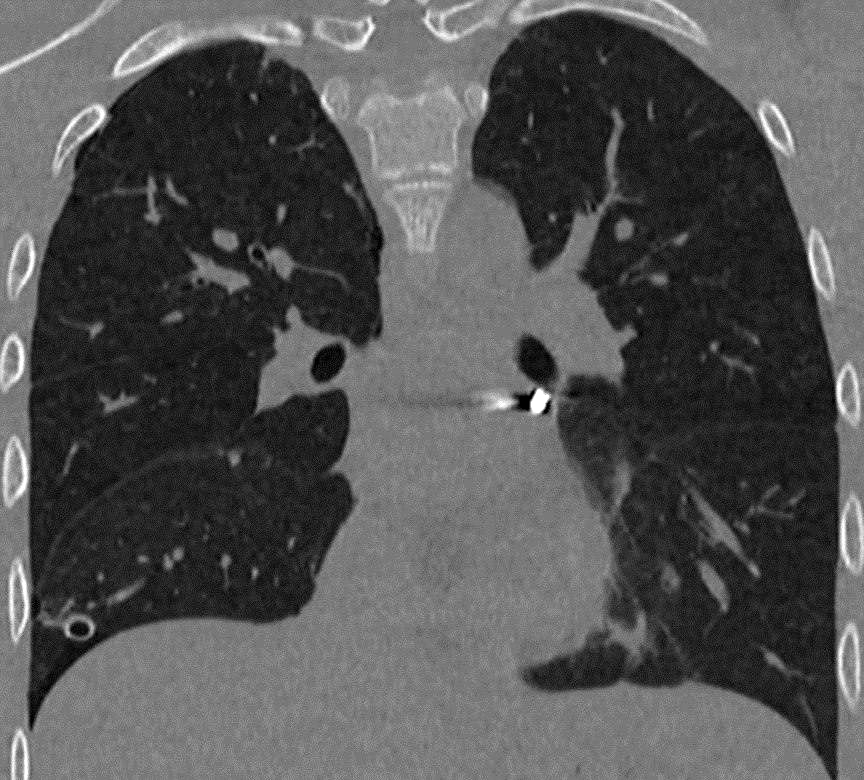

«Инородное тело мигрировало в опаснейшую зону — между легочными венами у задней поверхности предсердия. Мы выполнили малоинвазивную операцию со вскрытием перикарда, работая буквально в миллиметрах от жизненно важных структур», — рассказал заведующий отделением детской хирургии № 2 Никита Степаненко.